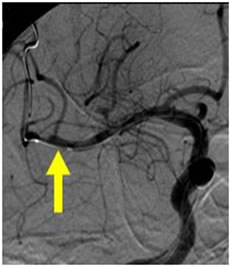

当院で行われた血栓除去術の実際の症例をお示しします。1例目は65歳男性、自宅にて動けなくなっているところを発見されました。軽度意識障害、重度の左片麻痺にて当院に救急搬送、NIHSS17点、心房細動を認めました。頭部MRI(図4)にて右大脳半球に矢印のように虚血巣の出現あり、MRA(図5)にて矢印のように右中大脳動脈の描出なく、緊急にて血管撮影を施行しました。バルーン付きのガイディングカテーテルを入れて、血栓より遠位にマイクロカテーテルを入れて、血栓の遠位からステント(Trevo provue 4×20mm)を展開後、血栓を回収しました。その後の撮影では閉塞していた血管はTICI2bまで再開通しており、治療直後から患者さんの左片麻痺は改善を認め、翌日のMRIでも梗塞巣は広範とならず、治療17日後に自宅退院しました。現在は社会復帰しており、元のお仕事にも戻っております。(図6、7、8、9参照)

図7:ステント回収後、閉塞血管は再開通しています。 |